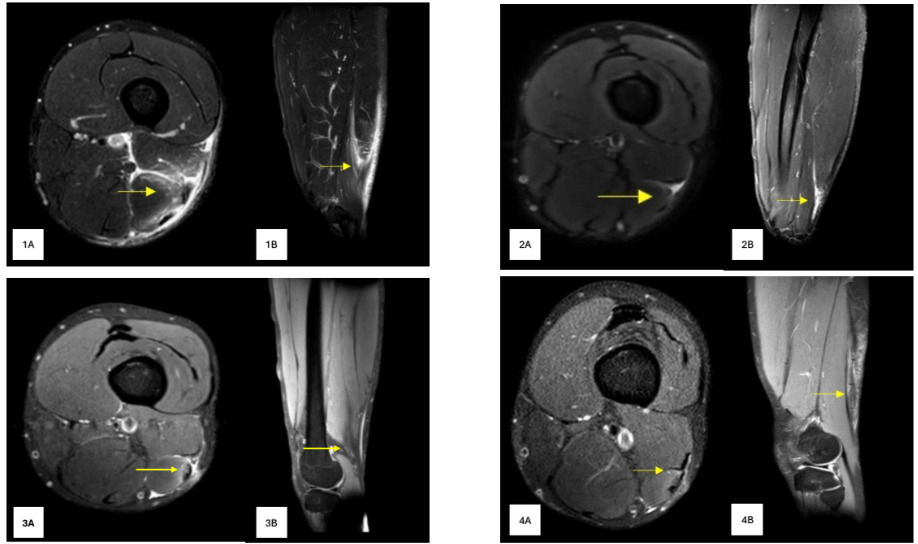

A 24-year-old male football player, playing in the Swiss first division, suffered an HSI during a friendly game while he was running at high speed with concomitant ipsilateral trunk rotation to press a defender waiting to receive the ball during the build-up phase (Supplemental Video 1). The first clinical decision was to undertake conservative treatment, which failed, and he suffered a re-injury in a match eight weeks after his first RTP. In this case, the subject did not report any acute mechanism of injury during the match. Twenty-four hours later the subject reported discomfort around the previous injury area. Following an MRI scan (magnetic resonance imaging, Figure 1) and an assessment by doctors, the orthopedic surgeon suggested a distal surgical repair. No ethics committee in place to provide ethical approval. An informed consent to publish signed by the patient was obtained. Patient confidentiality must be protected according to the U.S. Health Insurance Portability and Accountability Act (HIPPA).

After seeing the MRI, the surgeon recommended an operation for two main reasons: 1) chronic rupture, small seroma and gap identified at the biceps femoris (BF) T-Junction area with loss of tension of the musculotendinous structure; and 2) recurrent injury and failure of the conservative approach (Figure 1). In addition, given the player’s profile (fast and 1vs.1 player), this kind of injury probably would not have allowed him to perform at his pre-injury level, thus putting his professional career at risk.

At the beginning of week 16 the subject completed another isokinetic test (5 repetitions of concentric knee flexion/extension and 5 repetitions of eccentric knee extension at 60°/s and at 180°/s)27 (Figure 5). The isokinetic testing showed optimal values in concentric and eccentric hamstring strength (mean torque, peak torque and total work), with a side-to-side difference <10% between the injured and uninjured legs. A new MRI was also performed during the week, showing a good healing process (Figure 1). The process to this point has resulted in: 1) good tissue healing; 2) no substantial asymmetries in eccentric hamstrings strength at different velocities; 3) exposures under specific contexts at speeds ~ 95% of MSS; and 4) optimal participation with the team in various football exercises including HSR and sprint activities, all without negative symptoms or discomfort. On the basis on these outcomes, at 16 weeks post-surgery the player was allowed to return to on-field unrestricted training with the team(Online supplemental video 6).

The present study showed that after recurrent injury with a chronic rupture (small seroma and gap identified at the BF T-Junction area with loss of tension of the musculotendinous structure) a surgical repair was required (Figure 1). Taberner et al.9 reported in their study that after a high-grade semimembranosus proximal free tendon retracted tear in a professional soccer player, an orthopedic surgeon recommended an operative approach. In both cases, conservative treatment was dismissed due to the high risk of re-injury and negative consequences for an elite professional football player’s career.